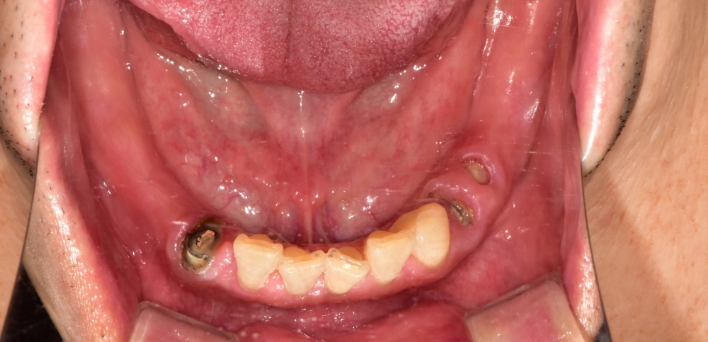

임플란트 : 손 ** 님 (50대)

Before Before

2020.02.30

After After

※ 더서울치과의원은 의료법을 준수하며 위 케이스는 실제 환자의 동의를 얻은 사례로 치료 전, 후가 동일한 환경에서 촬영되었습니다.

환자 케이스에 따라 부작용이 발생할 수 있습니다. 이 부분은 의료진의 충분한 상담과 체크를 통해 예방하고 줄일 수 있습니다.

[임플란트 부작용] 수술 후 관리가 소홀할 경우 출혈, 주위염 등의 부작용이 발생할 수 있어 구강 위생을 철저히 유지하고, 정기적인 검진을 통해 상태를 점검하는 것이 중요합니다.

환자 특징

환자 특징01무치악 상태

환자 특징02수년간 무치악으로 지내심

임플란트가 불가능할것이라

생각하고 내원

위, 아래 6개씩 식립

디지털 풀아치 임플란트